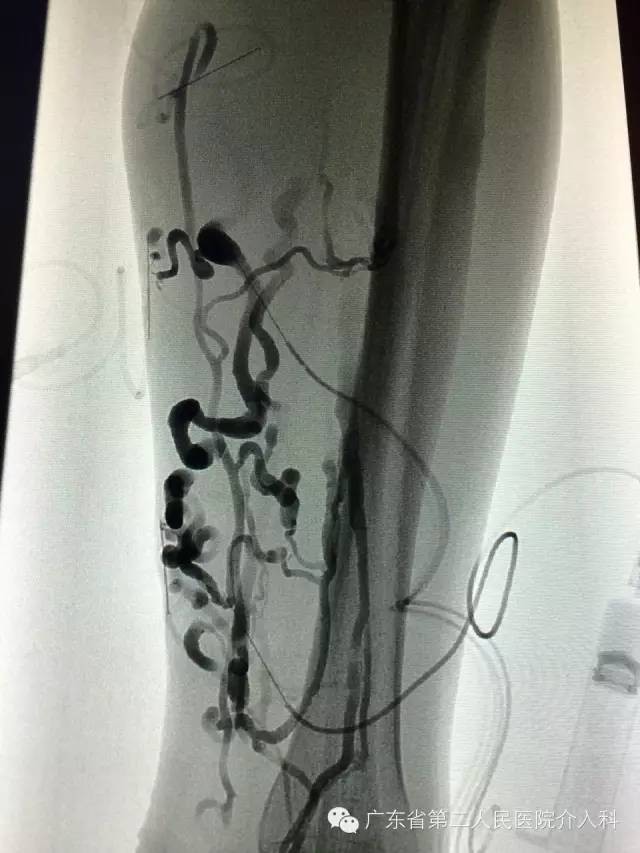

“蚯蚓腿”刚开始表现为静脉隆起、扩张、迂曲时,硬化治疗效果较好(如下图)。

静脉曲张导致的“蚯蚓腿”硬化治疗是如何进行的,创伤大不大?

硬化治疗是直接用细针穿刺曲张静脉注入泡沫硬化剂,达到使曲张静脉萎陷闭塞的治疗方法(如下图),术后弹力绷带加压或穿弹力袜辅助治疗。硬化治疗具有创伤小、可视化精准治疗、安全、疗效好、恢复快、并发症少等优点。硬化治疗后,患者可立即下床活动,不影响正常生活与工作。适合C1~C6期病人。